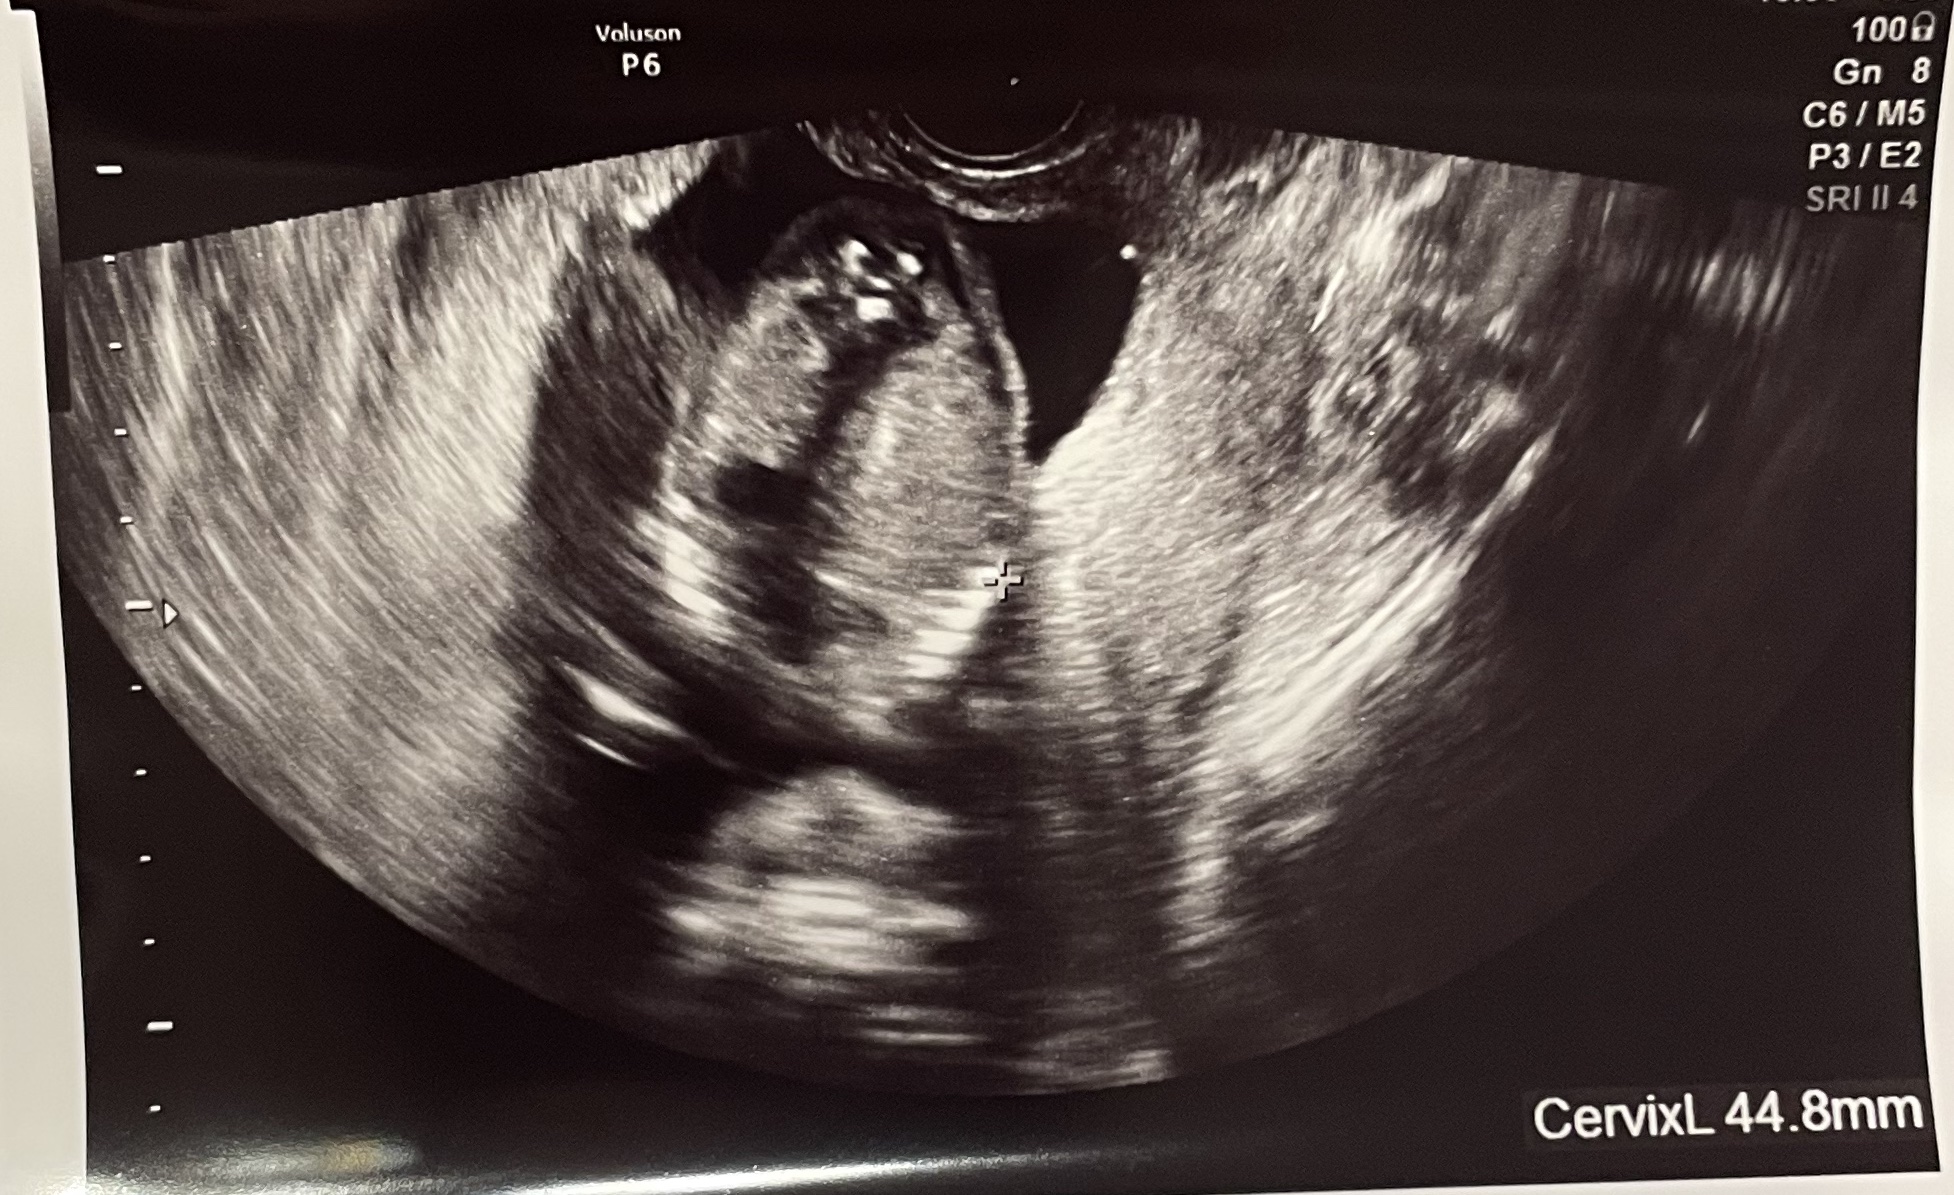

経膣エコー

赤ちゃんの姿も確認させてくれました。

前よりも大きくなっていて、目にした瞬間、すごく安心して涙が出そうになりました。

子宮頸管の長さや胎盤の位置も特に指摘されませんでした。